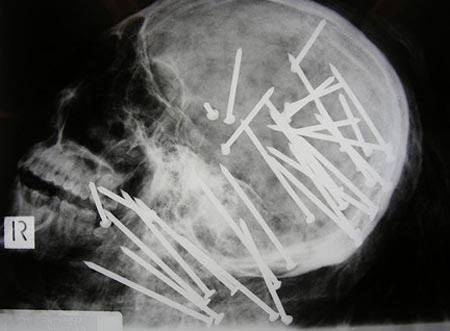

11. This looks photoshopped but holy crap it still makes me shudder.

15. Um, was this guy even still ALIVE!?!